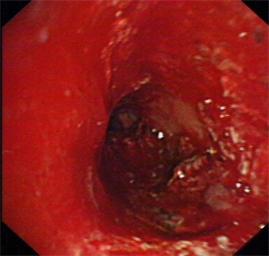

近日我科为一食道癌晚期、食道气道瘘的患者成功放置硅酮支架,患者在禁食1月后终于再次尝到了香甜的米饭,激动万分。该患者1年前在外院确诊为食道癌晚期,一直在我院放化疗科进行化疗及放疗,后患者逐渐出现进食后呛咳,复查胸部CT提示食道癌气道广泛侵袭,存在气道食道瘘可能。患者为避免进食后呛咳,已留置鼻饲,禁食1月。经我科俞万钧副院长会诊,决定为患者进行气道硅酮支架置入堵瘘口,让患者恢复进食。硅酮支架堵瘘术目前国际上开展不多,国内更是寥寥无几,手术难度大,成功率低。手术当日,俞万钧副院长亲自主刀,首先对气道浸润的肿瘤进行消融处理,后成功放置Y型硅酮支架,封堵瘘口。术后次日,患者就能进食流质,再次体会到进食的快乐。利用Y型气道硅酮支架封堵瘘口,全省目前未见报道,全国只有天坛医院,厦门二院等几家医院实施过,这一手术标志着我院硬镜,硅酮支架放置技术达到全国领先水平。(徐涛)